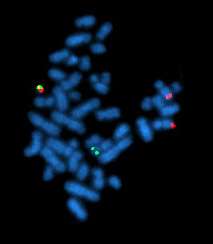

Philadelphia translocation t(9;22)(q34;q11.2) seen in chronic myelogenous leukemia.

In 1960, Peter Nowell and David Hungerford[21] discovered a small chromosome in the white blood cells of patients with Chronic myelogenous leukemia (CML). This abnormal chromosome was dubbed the Philadelphia chromosome - as both scientists were doing their research in Philadelphia, Pennsylvania. Thirteen years later, with the development of more advanced techniques, the abnormal chromosome was shown by Janet Rowley to be the result of a translocation of chromosomes 9 and 22. Identification of the Philadelphia chromosome by cytogenetics is diagnostic for CML.